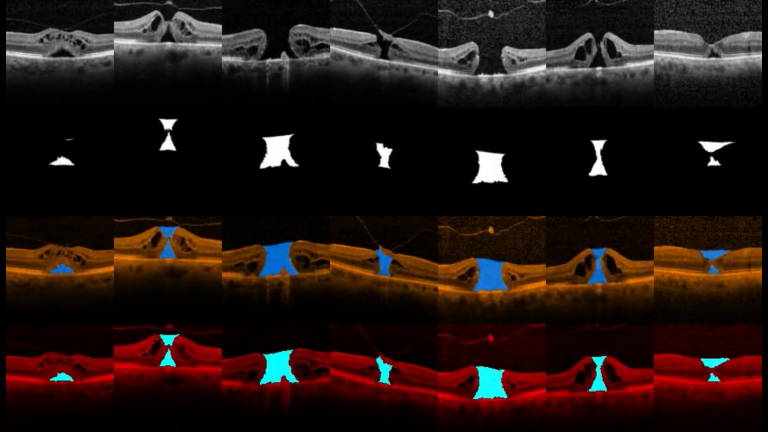

Biomedical Data Annotation: An OCT Imaging Case Study

We evaluate the quality of diabetic macular edema (DME) intraretinal fluid (IRF) biomarker image annotations on OCT B-scans from five clinicians with a range of experience. Our investigation shows a notable variance in annotation performance, with a correlation that depends on the clinician's experience with OCT image interpretation of DME.

External Limiting Membrane

We design a new benchmark for the segmentation of the retinal external limiting membrane (ELM) using an image dataset of spectral domain optical coherence tomography (OCT) scans in a patient population with idiopathic full-thickness macular holes. Then, we compared qualitative and quantitative results with seven state-of-the-art machine learning-based segmentation methods to identify the ELM line with an automated system.

Macular Oedema

The objectives of this project are to develop and assess novel image analysis techniques of 3D OCT scans for volumetric assessment of different morphological patterns in diabetic macular oedema (DMO) such as: 1) Overall volume of the generalised outer retinal thickening in early DMO. 2) Volume of accumulated serous fluid under the neurosensory retina (SRF). 3) Residual volume of retinal tissue passing between the inner and outer plexiform retinal layers, which is an optimal measurement of potential residual macular function.